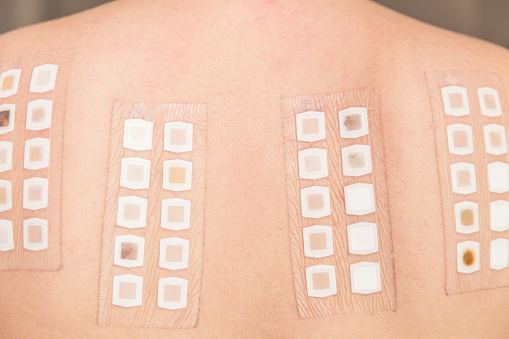

パッチテスト 皮膚科対応

金属アレルギーの可能性がある場合は、皮膚科にてパッチテストを実施し、アレルギー成分を特定します。

金属アレルギーは体全体に影響を及ぼす場合があります。特定のテストでアレルギー原因を突き止め、患者様の体質と症状に合わせた治療法を選択し、健康的な口内環境を目指します。少しでも不調を感じたら、お早めにご相談ください。

金属アレルギー治療の専門的なアプローチを提供します。初診から皮膚科紹介、パッチテスト、金属除去、アフターフォローまで一貫したケアで患者様の健康と安全を守ります。